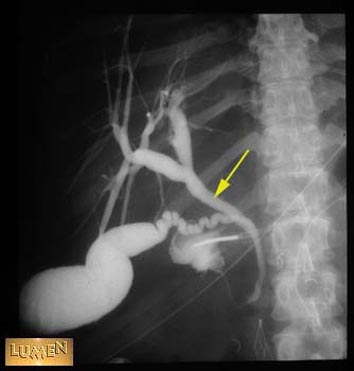

Question: Identify.

Answer

Common hepatic duct.